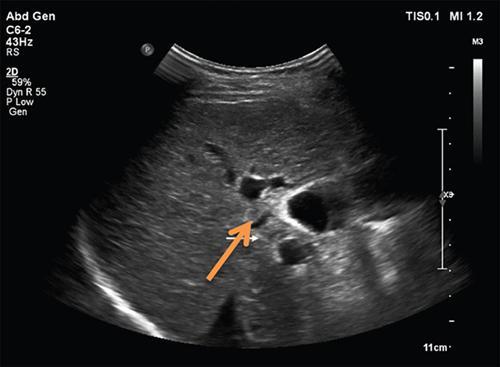

Ritu K. Kashikar, Shrinivas B. Desai, Payal Agrawal A spectrum of vascular variants can involve the liver. Both congenital and acquired anomalies can be seen. The abnormalities can involve the portal venous system, hepatic artery, hepatic veins or maybe the result of shunting between any of these vessels. Though not commonly encountered, familiarity with the pathogenesis and imaging features of these vascular entities can guide appropriate patient management. This chapter aims at classification of vascular pathologies of the liver (Table 9.12.1) with description of important entities. The umbilical vein accounts for approximately 80% of the afferent flow into the liver in utero. The umbilical vein joins the left portal vein, which in turn drains into the ductus venosus and carries blood to the inferior vena cava. The umbilical vein and ductus venosus start involuting at birth and typically close in the first week of life in term neonates (Fig. 9.12.1). Detailed embryology of the portal venous system has been discussed in previous chapters. The portal vein accounts for two-thirds of the hepatic blood supply. The distinctive feature of the portal vein is that it begins and ends in capillaries. The blood from the entire gastrointenstinal tract (except lower rectum), gallbladder, pancreas and spleen is carried via the portal vein to the liver. The hepatic arterial branches divide along the distribution of portal venous radicals and supply oxygenated blood to the sinusoids (Fig. 9.12.2). These include The dorsal and ventral limbs of the vitelline vein form the normal portal vein. Atrophy of the ventral limb occurs during embryogenesis. This maybe an incidental finding, though association with duodenal obstruction is seen in 50% cases. The aetiology of duodenal obstruction is often due to secondary causes such as duodenal stenosis, atresia, Ladd bands due to malrotation or annular pancreas. Associations include heterotaxy (polysplenia) and biliary atresia. Aberrant vessel may give an extrinsic impression on the high second portion of the duodenum on upper GI series. USG may show aberrant vessel in patients being scanned for other anomalies. The aberrant vessel is usually incidentally discovered intraoperatively during surgery for duodenal obstruction or malrotation. Hypoplasia or atresia of the portal vein may involve all or a portion of the portal vein. Atresia of a major branch is associated with absence of the corresponding hepatic lobe. Main portal vein hypoplasia or stenosis results in prehepatic portal hypertension and gastrointestinal hypertension (Flowchart 9.12.1). A portal vein smaller in calibre or as small as the adjacent hepatic artery is termed hypoplastic. The venous diameter in cases of hypoplasia is of 3 mm. Twenty-six per cent cases with biliary atresia have hypoplastic portal vein. TAPVR is a congenital cardiac malformation in which pulmonary veins instead of draining into left atrium during cardiac development, drain into the right atrium via an anomalous vein, resulting in right to left shunts. Types: In type 3 TAPVR an anomalous infradiaphragmatic vertical vein is formed by the confluence of pulmonary veins, typically through the oesophageal hiatus. Venous obstruction at the level of the diaphragm and accounts for the clinical presentation of pulmonary venous congestion and oedema. Early presentation (within 24–36 hours of life) included respiratory distress with cyanosis, tachypnea, and tachycardia. Features on X-ray include normal–sized heart with pulmonary interstitial oedema. One-third of patients have an additional complex cardiac anomaly and heterotaxy with right atrial isomerism. May show abnormal draining vein draining into the IVC or pulmonary vein. CT/MR venography allows accurate depiction of the anomaly. The pulmonary venous confluence drains to systemic veins below the diaphragm. The confluence is usually posterior to the left atrium and vertically oriented. From here, a descending vein passes through the oesophageal hiatus and most frequently drains into the connection in to ductus venosus, hepatic veins or inferior vena cava is not as frequent. Portosystemic shunts are classified into intrahepatic and extrahepatic. In the intrahepatic shunts, the shunt is at the level of PV branches after its division whereas in the extrahepatic shunts the anastomoses are between the tributaries of the portal or mesenteric system or main PV and a systemic vein (Flowchart 9.12.2). Abernethy malformation, also known as congenital extrahepatic portosystemic shunts (CEPS) is a rare clinical entity, in which portal blood is shunted partially or completely into the systemic circulation via an abnormal communication of the portal system with the systemic circulation. It results from persistence of embryonic vessels. The entity was named by John Abernethy in 1793. The embryological development of the portal vein occurs between the 4th and 10th weeks. The umbilical veins of chorionic origin, vitelline veins and the cardinal veins from the body of the embryo are the three paired venous systems seen in the embryo in the 4th week. Communications develop between the vitelline veins at 4 weeks, which anastomose to form a figure-of-eight configuration around the developing duodenum. Selective involution of these veins leads to the final configuration of the portal vein. Because the vena cava also has a complex development and is derived from several venous channels including the sinus venosus and a portion of the anastomosis between the right and left vitelline veins in the cranial part of the liver, it has been suggested that this may be the embryological basis of development of congenital extrahepatic portosystemic shunts. Various systems have been proposed for classification of Abernathy Syndrome: In this classification portal flow is classified as Patients with type A drainage show associated cardiac anomalies, while gastrointestinal bleeding is common in type C. In this system CEPS was classified into three types depending on the degree of severity of intrahepatic portal system hypoplasia in to mild, moderate and severe types. This system has therapeutic implications in providing information regarding acceptance of portal blood flow by the portal vasculature after shunt occlusion. CEPS may be asymptomatic well into adulthood and many authors have reported seeing adult patients presenting for the first time with clinical manifestations. Clinical features of portosystemic shunts may broadly be divided into: These include hepatopulmonary syndrome, metabolic dysfunction and hepatic encephalopathy. Patients with type 1 shunt have a female preponderance and often have concomitant congenital anomalies. These anomalies are less common in patients in type 2 shunts. Other anomalies have also been reported in patients with Abernethy malformation which include chromosomal anomalies such as Downs syndrome and structural anomalies of the heart, gastrointestinal, genitourinary, skeletal and vascular systems. Approximately half the patients of CEPS have nodular lesions of some sort in the liver (Flowchart 9.12.3). Nodular hepatic lesions in patients with congenital portosystemic shunts may be single or multiple. In order to establish a diagnosis of CEPS a communication between the portal and the systemic venous system, either before or after the formation of the PV by union of the SMV and SV has to demonstrated. Secondary causes of nonvisualization of the PV such as portal cavernoma or PV thrombus should be excluded. Patients with congenital portosystemic shunts do not have features of portal hypertension, such as splenomegaly, varices and collaterals. USG may demonstrate the shunt and show haemodynamics involved such as the magnitude and direction of flow. It may pick up congenital shunts preoperatively; however, it may not detect associated anomalies particularly of lung and heart. Smaller shunts, particularly type 1a may not be well picked up. Ultrasound may not fully characterize liver lesions seen in these patients. It is the modality of choice and can accurately diagnose the shunt and type and aids in management. Shunt is visualized as an abnormal communication between the portal venous and systemic circulation and is best depicted in the portal venous phase. CT also shows presence/absence of intrahepatic branches of portal vein. Evaluation of associated anomalies particularly in patients with congenital heart disease who require evaluation of pulmonary vasculature, or patients with suspected hepatopulmonary syndrome who require evaluation of the lungs can also be done with CT (Fig. 9.12.4 and Table 9.12.3). Another major advantage of CT is that it helps to detect and characterize hepatic lesions in these patients. It displays the arterial and venous anatomy, and provides an angiographic road map for surgical resection. Regenerative nodules are usually homogeneous with enhancement during arterial phase, on both CT, however without washout (Fig. 9.12.5). Rest of lesions show classic enhancement pattern as described in previous chapters. The imaging findings in patients with Abernethy malformation with hepatocellular carcinoma do not appear to be typical, that is hypervascularity on the arterial phase images with washout on delayed phase. Thus, patients who do not have typical findings of a benign lesion, that is lack of arterial enhancement, should be closely followed up or biopsied. Disadvantages of an MRI include longer periods of sedation which is a disadvantage in patients with CEPS who may be very young, very hypoxemic or encephalopathic. MRI also has lower spatial resolution than CT and may not show small intrahepatic portal venous radicles in type 2 patients. MRI can otherwise show all abnormalities seen on CT. Advantages of MRI using hepatobiliary contrast agents are in the characterization of hepatic nodules and for follow-up. MRI does not expose the patients to ionizing radiation. Patients with no symptoms, those with mild metabolic abnormalities and with liver nodules should be followed up with ultrasound and biochemistry. Patients with portosystemic encephalopathy, liver dysfunction or those with shunt ratio >60% should be treated according to type of shunt. Patients with type 1 shunts should be transplanted. Patients with type 2 shunts should be treated with shunt closure – either via embolization or surgical. Liver transplantation is considered when medical and surgical methods fail especially in patients with complications. Intrahepatic portosystemic shunts are rare. They may be congenital or result from trauma or portal hypertension. They develop due to persistent communications between vitelline and umbilical systems. These are communications between the branches of the PV and inferior vena cava (IVC). Park et al. classified these 1990 in four types. Type 5 was added later, these are classified in Table 9.12.4. Type 2 shunt with or without a focal varix is the most common type reported. Another classification system is proposed by Kanasawa et al. based on correlation with severity of portal hypoplasia (mild, moderate and severe) with portal venous pressure, histopathological findings, postoperative portal venous flow and hepatic regeneration. Associated anomalies such as cardiovascular, hepatobiliary, urogenital and gastrointenstinal can be seen. Complications such as portopulmonary hypertension are seen in 13%–66% children. As a consequence of long-term shunting, hepatic encephalopathy, and hepatopulmonary syndrome are the most common symptoms. Tumours such as FNH and regenerating nodular hyperplasia can be seen. These shunts may close spontaneously within the first 2 years of life or may remain asymptomatic and undetected for several years. When chronic shunting persists into adulthood, patients most often present with encephalopathy. The feeding (afferent) and draining (efferent) vessels of the shunt appear as enlarged, tubular, anechoic structures that are contiguous with the portal and hepatic veins. Antegrade flow is seen on colour Doppler images. Focal varix if present appears as an abnormal, rounded cystic structure with turbulent flow. Doppler study can also calculate the shunt ratio (total blood flow volume in the shunt divided by the blood flow in the portal vein). Shunt ratios greater than 60% should be corrected to prevent complications. Loss of normal undulating waveform of afferent portal vein branch with increased flow velocity and phasic waveforms owing to transmitted cardiac pulsations can be seen. The efferent hepatic vein branch of the shunt can show continuous flow with flattening of the Doppler waveform due to increased portal venous inflow. Communication between intrahepatic portal venous and peripheral hepatic venous radicals can be demonstrated easily on both contrast-enhanced CT and MRI. Similar to extrahepatic shunts CT is preferred over MRI in documentation of shunts. The afferent portal vein branch and the efferent hepatic vein branch are enlarged. Venous varices can be seen. The draining hepatic vein branch opacifies earlier than other hepatic veins (Fig. 9.12.6 and Table 9.12.5). The liver may show fatty degeneration and atrophy, but when the anomaly is corrected, fatty replacement disappears and liver size increases. Conservative medical therapy including restriction of protein and ingestion of lactulose. Symptomatic intrahepatic portosystemic shunts can be managed conservatively or with transcatheter embolization, surgical ligation or partial hepatectomy. The connection between the left umbilical vein and right hepatocardiac vein (future IVC) in the foetal circulation is called ductus venosus. This vessel is responsible for carrying nutrient-rich blood from placenta to the right atrium directly by bypassing the sinusoidal plexus of the liver. The umbilical vein and ductus venosus close at birth and form the ligamentum teres and ligamentum venous, respectively. The time interval following birth for closure of ductus venosus is variable ranging from few minutes after birth to 18 days in term neonates and as late as 37 days in premature infants. Patent ductus venosus is an intrahepatic portocaval shunt causing partial or complete diversion of portal blood to the systemic circulation and may present with hyperammonemia. Patent ductus venosus is seen on Doppler sonography as a vascular tubular structure in the left lobe of the liver, continuing from the umbilical vein and connecting the portal vein to the inferior vena cava. The foetal ductus venosus show waveforms similar to IVC corresponding to the cardiac cycle with a systolic and diastolic component. This diphasic waveform is seen in preterm and term infants and becomes monophasic as ductus closes. CT and MRI also accurately detect the shunt and patency. Associated hepatic lesions seen in patients with portosystemic shunts can be diagnosed and characterized better. Treatment (closure) is recommended in cases with complications or to prevent complications if the shunts persisted beyond 2 years of age. Shunt closure can be performed surgically or endoscopically. The complex nature of the shunt can pose problems during surgical closure. Transvenous and balloon occlusion have been done successfully. Occlusion of portal vein can occur due to a variety of conditions. The aetiologies of portal venous thrombosis in the neonatal age group include umbilical vein catheterization, omphalitis, dehydration or neonatal sepsis. Older children develop occlusion secondary to intraabdominal infections and portal hypertension. Other aetiological factors include prothrombotic states such as hereditary deficiency of protein C or protein S and factor V Leiden deficiency, vascular injury, trauma, stasis and congenital anomalies such as webs. Acute portal vein thrombosis can be asymptomatic, or the patient may present with abdominal pain, ascites or fever. Chronic portal vein thrombosis presents as ascites, encephalopathy, varices and upper gastrointestinal bleeding. Acute thrombus appears hypoechoic filling defect on USG with absent flow on Doppler. There is distension of the thrombosed vein (Fig. 9.12.7). CT and MRI with contrast will detect filling defect in the vein with distension. T2W1 images may show absence of flow void. Acute thrombus may appear hyperintense on T1W1 images. Tumour thrombus reveals signal similar to tumour on all sequences with diffusion restriction (Fig. 9.12.8). Chronic thrombus may present as eccentric filling defect, attenuation of vein or less commonly calcification of vessel wall. Collaterals are often seen in chronic portal vein thrombosis. Treatment usually involves combination of anticoagulation and intervention depending on age of thrombus. An acute portal venous thrombus may undergo partial or complete spontaneous resolution. The commonest cause of paediatric portal hypertension in the developing world is extrahepatic portal vein obstruction (EHPVO). It is also the second most common cause of portal hypertension in the western world. EHPVO is a condition characterized by obstruction of the extrahepatic portal vein (as the name suggests) with or without associated involvement of the intrahepatic branches, splenic vein (SV) or superior mesenteric vein (SMV). The hallmark of this chronic longstanding condition is carvernomatous transformation of the portal vein. Acute and chronic portal vein thromboses occurring in the setting of liver cirrhosis or HCC are not included in this disorder. EHPVO is an important cause of noncirrhotic portal hypertension with preserved liver structure and function till late in course of the disease. Proposed aetiologies include infection or prothrombotic event occurring early in life (in genetically predisposed individuals), leading to portal venous occlusion (Table 9.12.6).